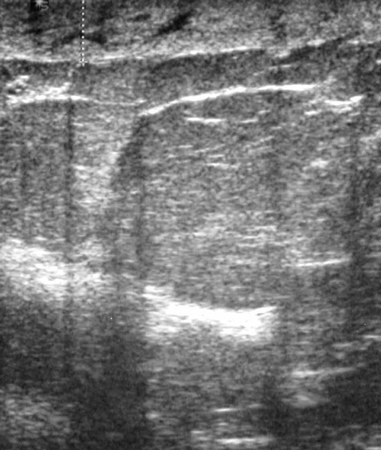

Los quistes simples son totalmente anecoicos, se diferencian del tejido mamario circundante al realizar un ultrasonido de mama y son benignos.[18][Figure caption and citation for the preceding image starts]: Imagen en ultrasonografía de un quiste simpleCortesía del Dr. Lane Roland, University of Louisville; utilizada con autorización [Citation ends].